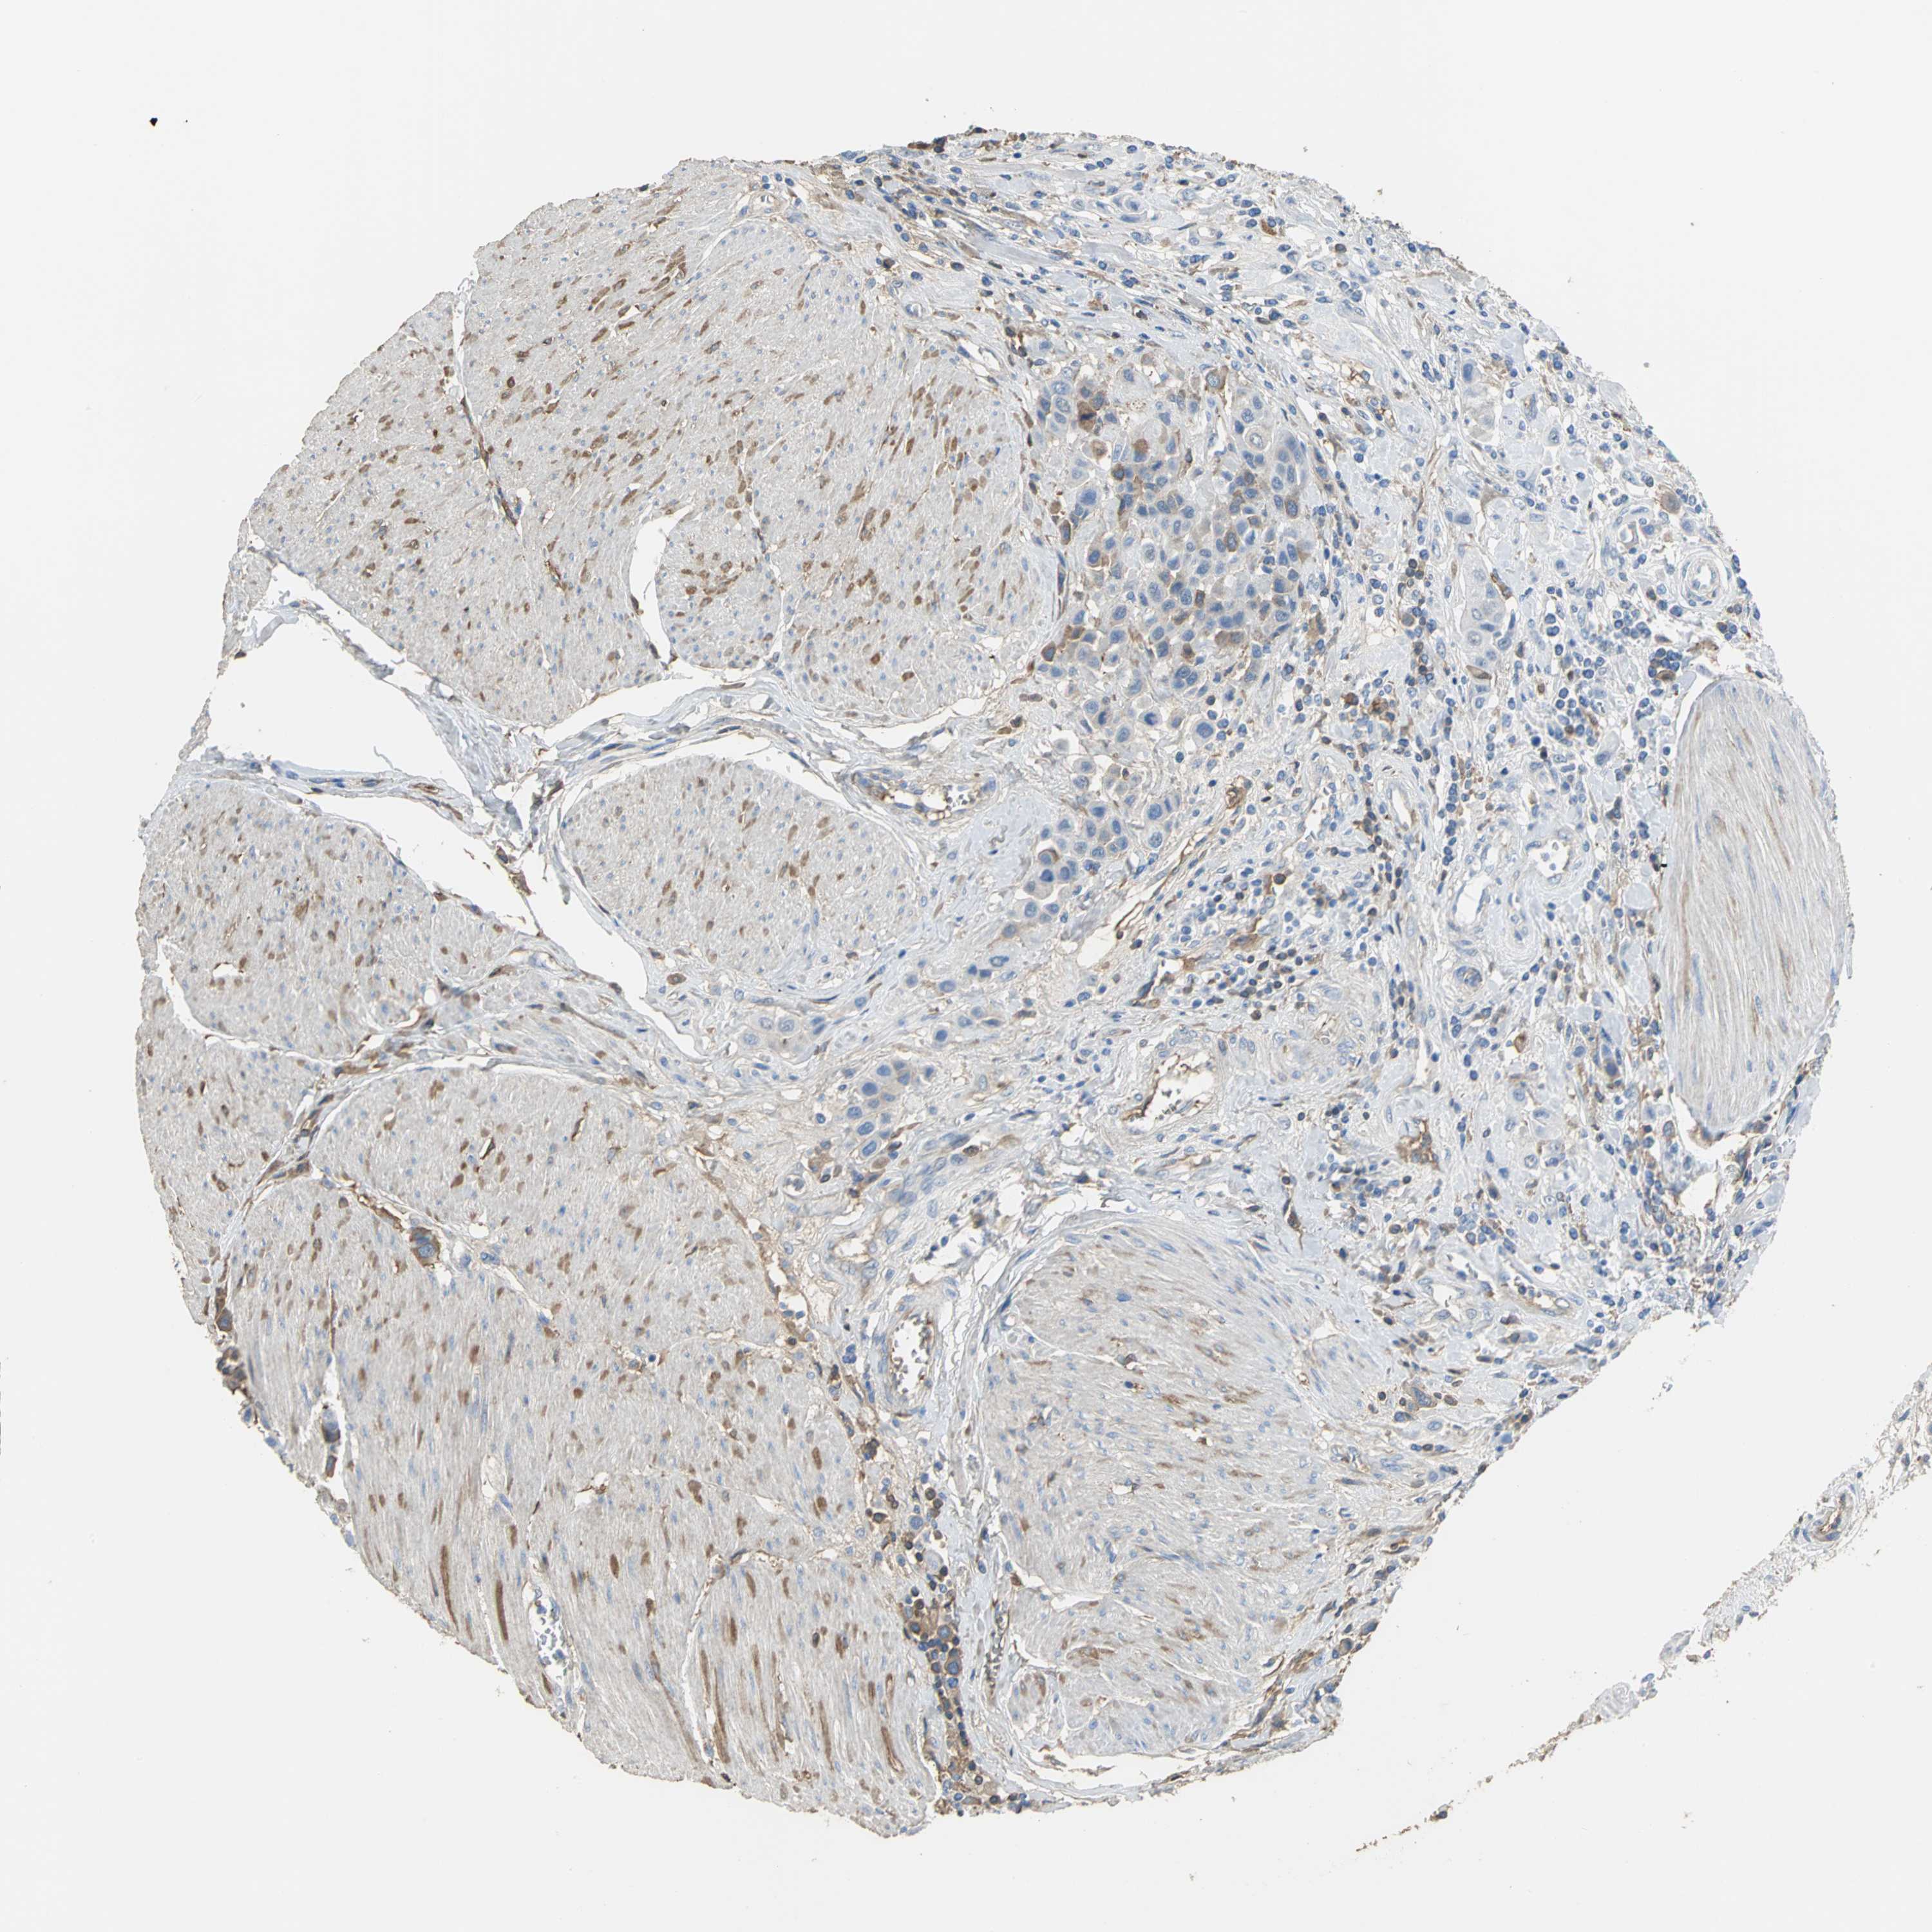

UROTHELIAL CANCER - Protein expressioni

A mouse-over function shows sample information and annotation data. Click on an image to view it in a full screen mode. Samples can be filtered based on level of antibody staining by selecting one or several of the following categories: high, medium, low and not detected. The assay and annotation is described here.

Note that samples used for immunohistochemistry by the Human Protein Atlas do not correspond to samples in the TCGA dataset.

Antibody stainingi

Antibody staining in the annotated cell types in the current human tissue is reported as not detected, low, medium, or high, based on conventional immunohistochemistry profiling in selected tissues. This score is based on the combination of the staining intensity and fraction of stained cells.

Each image is clickable and will lead to virtual microscopy that enables deeper exploration of all samples and also displays staining intensity scores, fraction scores and subcellular localization as well as patient and tissue information for each sample.

Antibody HPA005495

Antibody HPA064686

Staining

High

Medium

Low

Not detected

Intensity

Strong

Moderate

Weak

Negative

Quantity

>75%

75%-25%

<25%

None

Location

Nuclear

Cytoplasmic/membranous

Cytoplasmic/membranous,nuclear

Urothelial carcinoma, High grade

Urothelial carcinoma, Low grade

Urothelial carcinoma, NOS